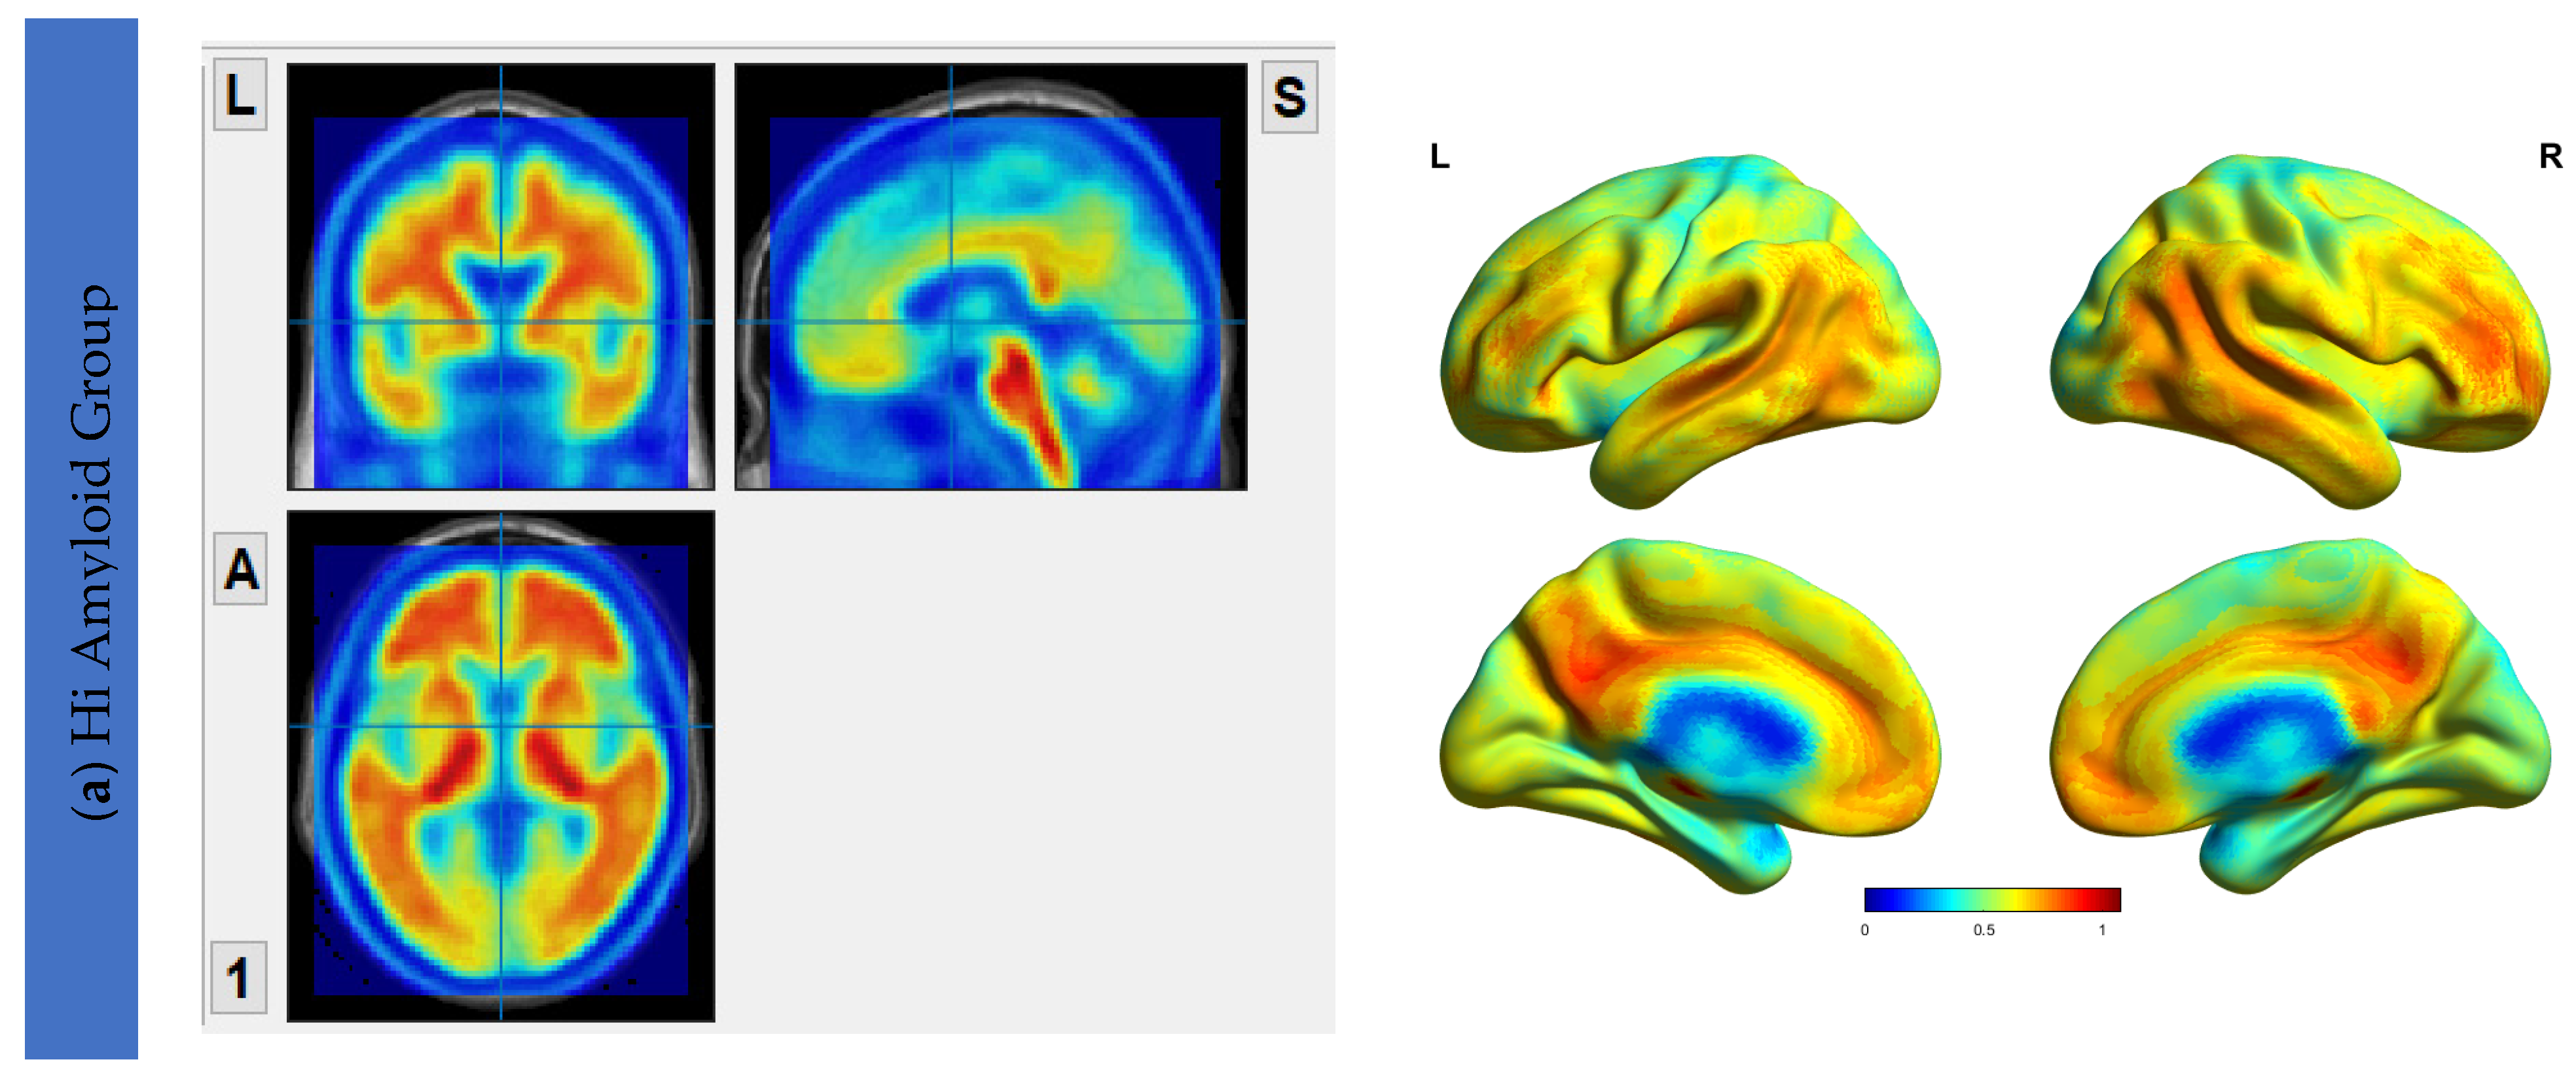

6.2. Aβ Protein Accumulation (SUVr) Maps

6.3. Interhemispheric Functional Connectivity (VMHC) Maps